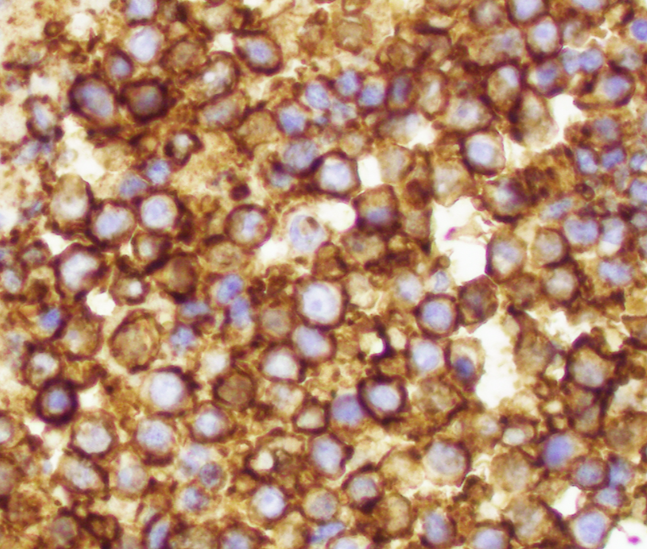

Microscopic (histologic) images

Positive stains

- CD99 (strong, diffuse membranous expression in ~90 - 95%) (Am J Surg Pathol 2005;29:1025)

- NKX2.2 (high specificity) (Am J Surg Pathol 2012;36:993)